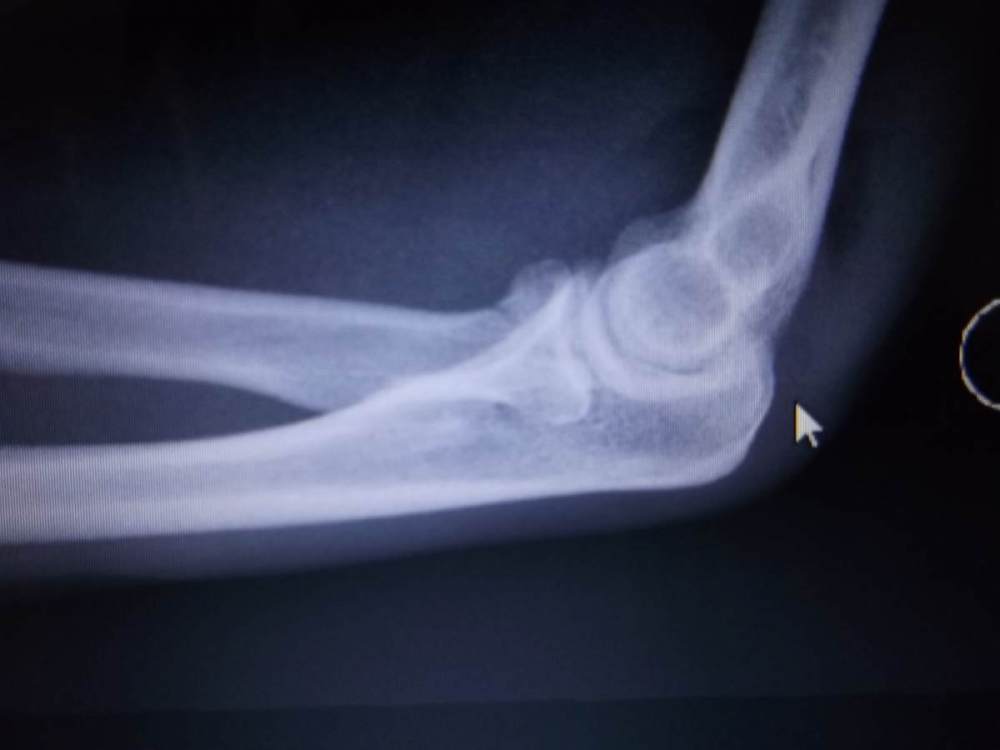

abra Napisano 12 Czerwca 2021 Napisano 12 Czerwca 2021 Jestem wkurzony na siebie jak nigdy. Kiedyś to się musiało wydarzyć i zdarzyło się dziś. Pofolgowałem sobie i poszarżowałem po przełęczy Jaworzynka (nad Wierchomlą). Zapieprzałem po trawiastym szlaku zbyt blisko poprzedzającego mnie kolegi. W pewnym miejscu pojawiły się głębokie wyschnięte rowy z jakiegoś zakopanego auta terenowego, których będąc za kimś zbyt blisko, nie dostrzegłem . Kolega odbił w bok a ja do koleiny na której końcu był kamol wielkości psa (pewnie podkładali jak odkopywali auto). Wpadając do koleiny próbowałem wytracić prędkość ale wszystko trwało ułamek sekundy gdy na tym kamyrdolu zrobiłem klasyczną przelotkę przez kierownicę przy dość sporej prędkości . Efekt - zwichnięty lewy łokieć, zwichnięty prawy nadgarstek, stłuczone prawe kolano, skrzywiony hak przerzutki (trochę się dało naprostować żeby w ogóle dalej jechać). Pętla została skrócona, jakoś stoczyłem się na dół, na stromszych fragmentach schodząc obolały. Popsułem wycieczkę żonie i koledze, najgorsze że raczej szlag trafił nasz wyjazd na forumowy zlot 😥. Najgorszy ten łokieć, napuchł i nie wygląda żeby kontuzja miała się wyleczyć w ciągu 5 dni. Jestem idiotą! Szkolny błąd! Jak nie widzisz ścieżki przed sobą to nie pędź😣! Sam drę się do żony, by zachowała za mną dystans , żebym nie zasłaniał jej obserwacji ścieżki, żeby był czas na reakcję. Stary i głupi 👎. Druga poważna kontuzja w tym sezonie. Pierwsza - pęknięcie żebra, ok przypadek. Tutaj już ewidentnie moja głupota. 😔 Cytuj

marvelo Napisano 21 Czerwca 2021 Napisano 21 Czerwca 2021 Czasem zwichnięcia są gorsze niż złamania. Ja miałem 4 lata temu złamanie głowy kości promieniowej (na szczęście bez przemieszczeń, więc operacji nie było) i jeden chirurg uprzedzał mnie, że mogę już tej ręki nigdy nie wyprostować. Drugi kazał zdjąć gips po góra 10-u dniach (zdjąłem po 9-u) i zacząć już lekko ćwiczyć. Teraz nie mam nawet śladu ograniczenia ruchomości, ani w wyproście, ani w rotacji. Gdybym posłuchał tego pierwszego i nosił gips przez miesiąc, pewnie pełnego wyprostu już bym nie osiągnął. Brambosz, miałeś to składane operacyjnie? Długo miałeś unieruchomienie? Cytuj

marvelo Napisano 21 Czerwca 2021 Napisano 21 Czerwca 2021 Oczywiście, że zdjęcie kontrolne było. Ten drugi lekarza kazał je zrobić po zdjęciu gipsu. Ręka była już całkiem sztywna i dwa razy chudsza, choć to tylko 9 dni. Wypadek miałem 29.06.2017, w czwartek wieczorem. Wróciłem rowerem do domu, po czym pojechałem samochodem na SOR, gdzie prześwietlili tylko głowę i stwierdzili złamanie nosa. Ręka bolała, ale jeszcze się ruszała. W piątek nie dostałem się do chirurga, z daleka popatrzył i kazał przyjść w poniedziałek. Dopiero wtedy zrobili mi rtg i wyszło to złamanie w łokciu.Ręka bolała w każdej pozycji, była już mocno spuchnięta i zakresu ruchu już nie miałem żadnego. Pierwsze zdjęcie z poniedziałku (03.07), prawie cztery doby od urazu. Kolejne z 12.07, czyli trzynaście dni od urazu. Nie widać już linii złamania. Dołączam tez opis. Nie wiem, może cud, a może efekt zażywania preparatu Osteogenon (ten drugi lekarz mi go przepisał), w każdym razie już się zalało kostniną. Oczywiście tej ręki po zdjęciu gipsu nie obciążałem, ale na temblaku nosiłem tylko czasami. Próbowałem prostować i zginać w granicach lekkiego bólu, intuicyjnie. Pełny wyprost osiągnąłem może po trzech miesiącach, głównie przez wieszanie się na drążku. Cytuj

Brombosz Napisano 21 Czerwca 2021 Napisano 21 Czerwca 2021 7 godzin temu, marvelo napisał: Brambosz, miałeś to składane operacyjnie? Długo miałeś unieruchomienie? Miałem dokładnie to samo co ty. Złamanie kości promieniowej u nasady bez przemieszczenia, po upadku na łeb z ok. 2m. Bawiłem się dalej, wypiłem jakieś tam 4% i na SOR poszedłem nad ranem drugiego dnia. Tu historia dopiero się zaczyna, bo tam doktor dyżurna 70 lat+ z okularami od Stępnia nie zauważyła złamania i chodziłem potem tydzień z ręką w szmacie nazwanej temblakiem. Dopiero po tygodniu miałem się zgłosić do ortopedy bo taką mi wyznaczono datę i tamten się połapał pakując mi rękę w gips na dwa tygodnie. Ogarnąłem się w moment. Jeździłem już z gipsem, a po 4 miesiącach mogłem robić normalne treningi łącznie z drążkiem. Jedynie te kilka mm brakujące do wyprostu ręki zauważam, ale to tylko kiedy chcę bo nie przeszkadza mi to w niczym. Zdjęć nie wklejam bo masz takie same. Cytuj